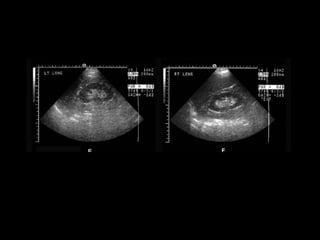

A bedside sonogram was performed and the gallbladder could

not be confidently identified. The patient was sent to the radiology

department for another abdominal ultrasound study. Selected

ultrasound images, including the right upper quadrant,

are shown in Figure 1.

Abdominal examination revealeddiminished bowel sounds, moderate tenderness in the right upper quadrant, and a Murphy’s sign. There was no tenderness on rectal examination and stool was guiac negative. An intravenous line was started and blood specimens were obtained. Intravenous fluids, insulin, and ampicillin/sulbactam were administered Blood test results (units for electrolytes, mEq/L and chemistry values, mg/dL, except where noted): WBC 19,700/mm3, hematocrit 49%, platelets 246,000/mm3. Na 132, K 4.1, Cl 101, CO2 22, BUN 24, creatinine 1.4, glucose 406. ALT 100 U/L (normal: 7–37), AST 65 U/L, alkaline phosphatase 61 U/L (normal: 39–117), total bilirubin 1.6 (normal: 0.2–1.2), lipase 110 U/L (normal). A bedside sonogram was performed and the gallbladder could not be confidently identified. The patient was sent to the radiology department for another abdominal ultrasound study. Selected ultrasound images, including the right upper quadrant, are shown in Figure 1.